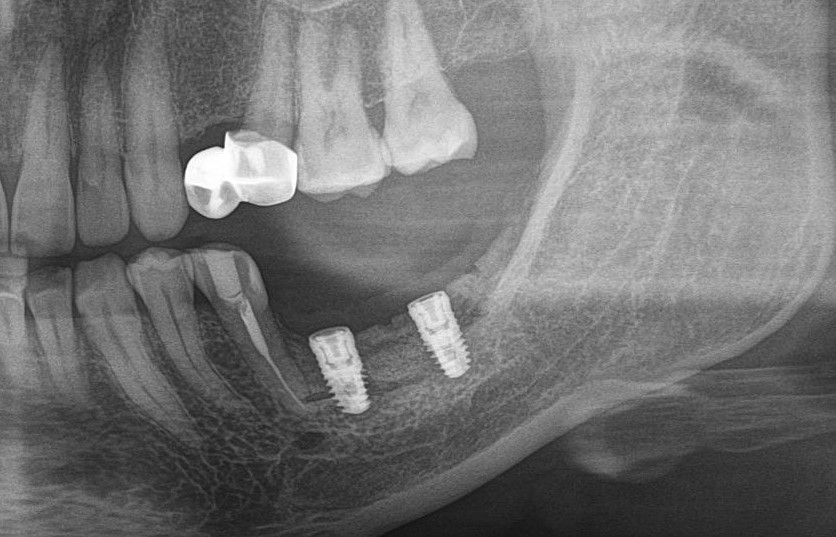

После операции:

— контрольный снимок (раньше делали ОПТГ, сейчас — строго КЛКТ)

Для этого мы сделали КЛКТ:

И КЛКТ показала нам, что с имплантатами и окружающей костью всё зашибись. Через 12 лет после операции, отсутствия наблюдения, пофигизма в замене временных коронок! Нужны ли тебе еще какие-нибудь доводы в пользу долгосрочной эффективности метода?